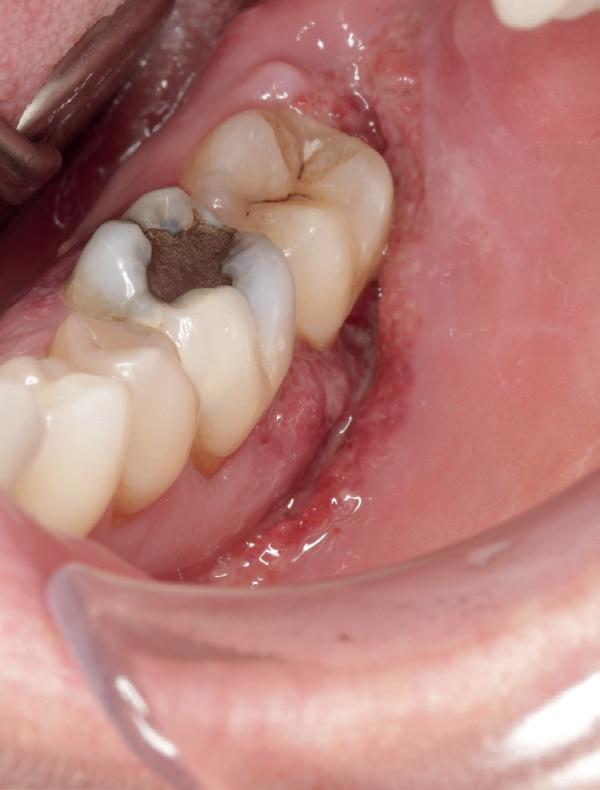

De patiënt werd in de eerste fase gezien door de parodontoloog, implantoloog en restauratief behandelaar. Klinisch werden drie complicerende factoren vastgesteld: inadequate mondhygiëne, een ongunstige occlusale relatie en restauraties met gebrekkige marginale adaptatie met overhang. De patiënt werd opgenomen in het parodontale behandelprotocol.

De diagnose luidde lokaal parodontitis met ernstige furcatie aandoeningen; Stadium IV (vergevorderd); graad C (snel progressief) (afbeelding 7) De elementen die niet te behouden waren, werden geëxtraheerd.

Tijdelijke voorzieningen werden getroffen in de vorm van een etsbrug in de bovenkaak en een uitneembare voorziening voor de onderkaak.